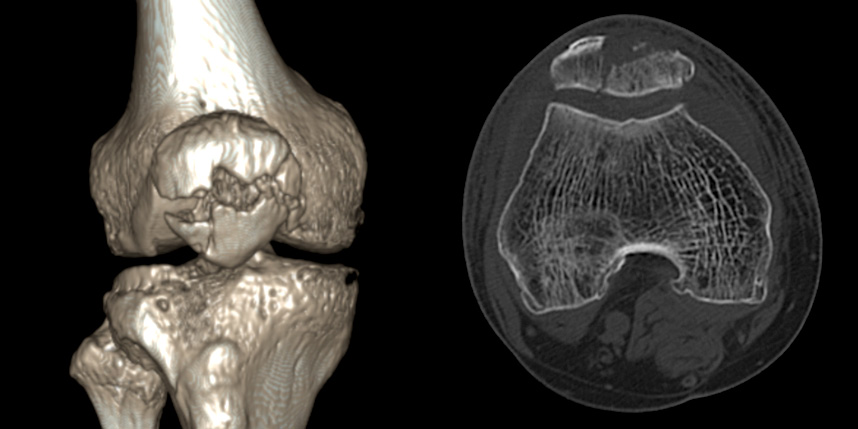

무릎 골절